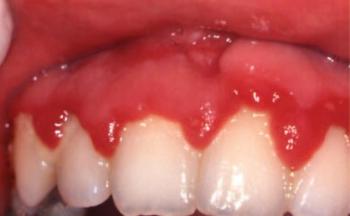

Klinikai kép. A gingivostomatitis herpeticás beteg anamnézisében szerepel herpeszes személlyel való találkozás. Az elsődleges (prodromális) tünetek: magas láz 38,5–39 0C gyengeség, fáradékonyság, izomfájdalom és néha torokfájás. Ebben a korai szakaszban a nyaki nyirokcsomók duzzadtak és érzékenyek lehetnek. A prodromális stádium 1-2 napig tart, majd megjelennek az orális és néha a periorális léziók (6.2. ábra, 6.3. ábra).

6.2. ábra. Gingivostomatitis herpetica

Vesiculák jelennek meg a szájnyálkahártyán, amelyek a nedves környezetben hamar felrepednek és felületes eróziók maradnak vissza. Bár a vesiculák viszonylag kicsik, az összefolyó vesiculák felrepedése nagy, fájdalmas fekélyeket okoz. Herpeslézió a szájban bárhol megjelenhet, de leggyakoribb az ajkon és az orr alatt. A fekélyes területeken kívül a gingiva gyulladt, a nyelven, a buccán, a palatumon vesiculacsoportok észlelhetők. Az egész szájnyálkahártya enyhén hyperaemiás és fájdalmas. Felnőttkorban jelentkező fertőzés hematológiai betegségekre (leukaemia) és immunhiányos állapotokra hívhatja fel a figyelmet, ezért a beteget laborvizsgálatra kell küldeni. A felnőttkori megjelenés gyakori oka lehet még, hogy a beteg hosszabb ideig ki volt téve ultraibolya sugárzásnak (napozás) vagy a beteg enyhén immunhiányos. Az intraorálisléziók mellett a vesiculák megjelenhetnek az ajkon és a száj körüli bőrön, és mivel a bőr viszonylag stabilabb, mint a szájnyálkahártya, a vesiculák tovább megmaradnak. Ritkán a primer HSV-fertőzés szóródhat, átjutva a vér-agy gáton életet veszélyeztető meningitist vagy encephalitist okozhat. Ez főleg súlyos immunhiányos személyeken fordul elő (nem jelent feltétlenül AIDS-et).